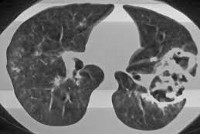

Основополагающую роль в установлении диагноза играют результаты рентгенологического обследования. Вместе с тем, стандартная рентгенография легких не всегда позволяет визуализировать небольшие полостные образования на фоне пневмонической инфильтрации. Поэтому при подозрении на абсцедирующую пневмонию целесообразно прибегать к проведению КТ грудной клетки. В случае формирования абсцесса легкого на снимках определяется толстостенное полостное образование с наличием характерного уровня жидкости и газа.

Основополагающую роль в установлении диагноза играют результаты рентгенологического обследования. Вместе с тем, стандартная рентгенография легких не всегда позволяет визуализировать небольшие полостные образования на фоне пневмонической инфильтрации. Поэтому при подозрении на абсцедирующую пневмонию целесообразно прибегать к проведению КТ грудной клетки. В случае формирования абсцесса легкого на снимках определяется толстостенное полостное образование с наличием характерного уровня жидкости и газа.